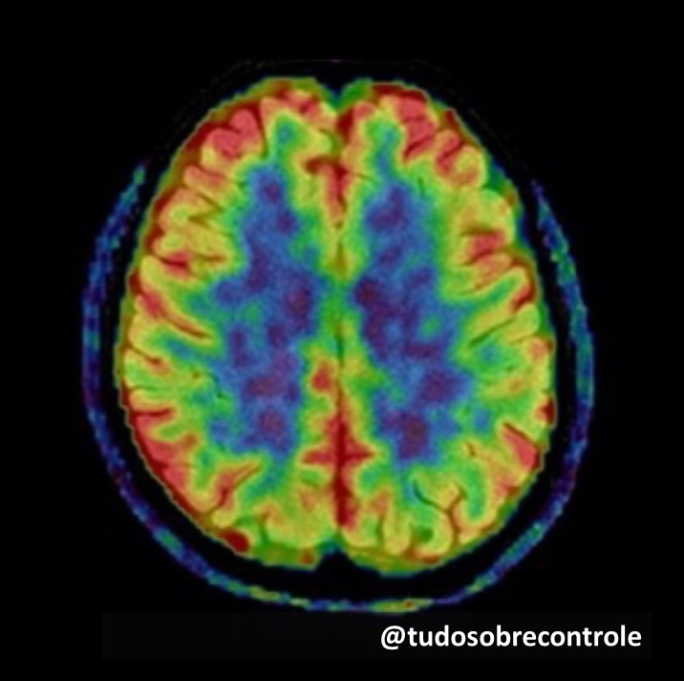

O resultado explica porque os pacientes mesmo após a total cicatrização do ligamento tendem a não confiar no joelho e a o movê-lo de maneira diferente, o que aumenta a chance de novas lesões e dificulta o retorno às atividades. Ressonâncias magnéticas do cérebro desses pacientes mostraram que quando eles são pedidos para movimentar o joelho são ativadas apenas áreas visuais e não mais áreas de sensibilidade do joelho. O cérebro confia apenas na informação visual do movimento do joelho e esquece da informação da sensibilidade. Acontece algo parecido conosco quando andamos no escuro: não sentimos onde estão os móveis e nos movemos bem mais lentamente e com medo de nos machucar. Esses indivíduos com lesão no ligamento fazem o mesmo: andam devagar e usando a visão sem necessidade.